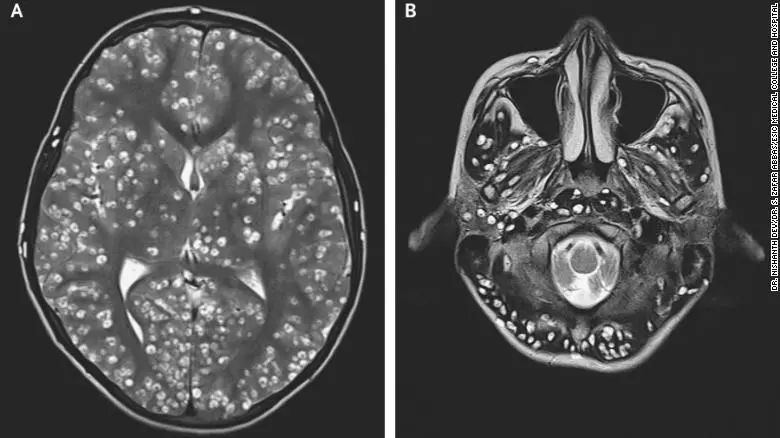

寄生虫导致的脑囊肿

长期头痛照x 光像「芝麻饼」?脑内满布寄生虫全因饮食习惯_虫卵